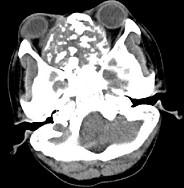

问题 男性,28岁,因鼻塞、头痛1年余,鼻窦CT扫描如图所示,请选择正确的描述与结论()

选项 A.双侧上颌窦、筛窦、鼻腔及蝶窦内见软组织肿块影 B.肿块内密度不均,有较多致密钙化影 C.窦壁及颅底骨质破坏 D.考虑鼻窦骨瘤 E.考虑为鼻窦软骨瘤

答案 ABCE